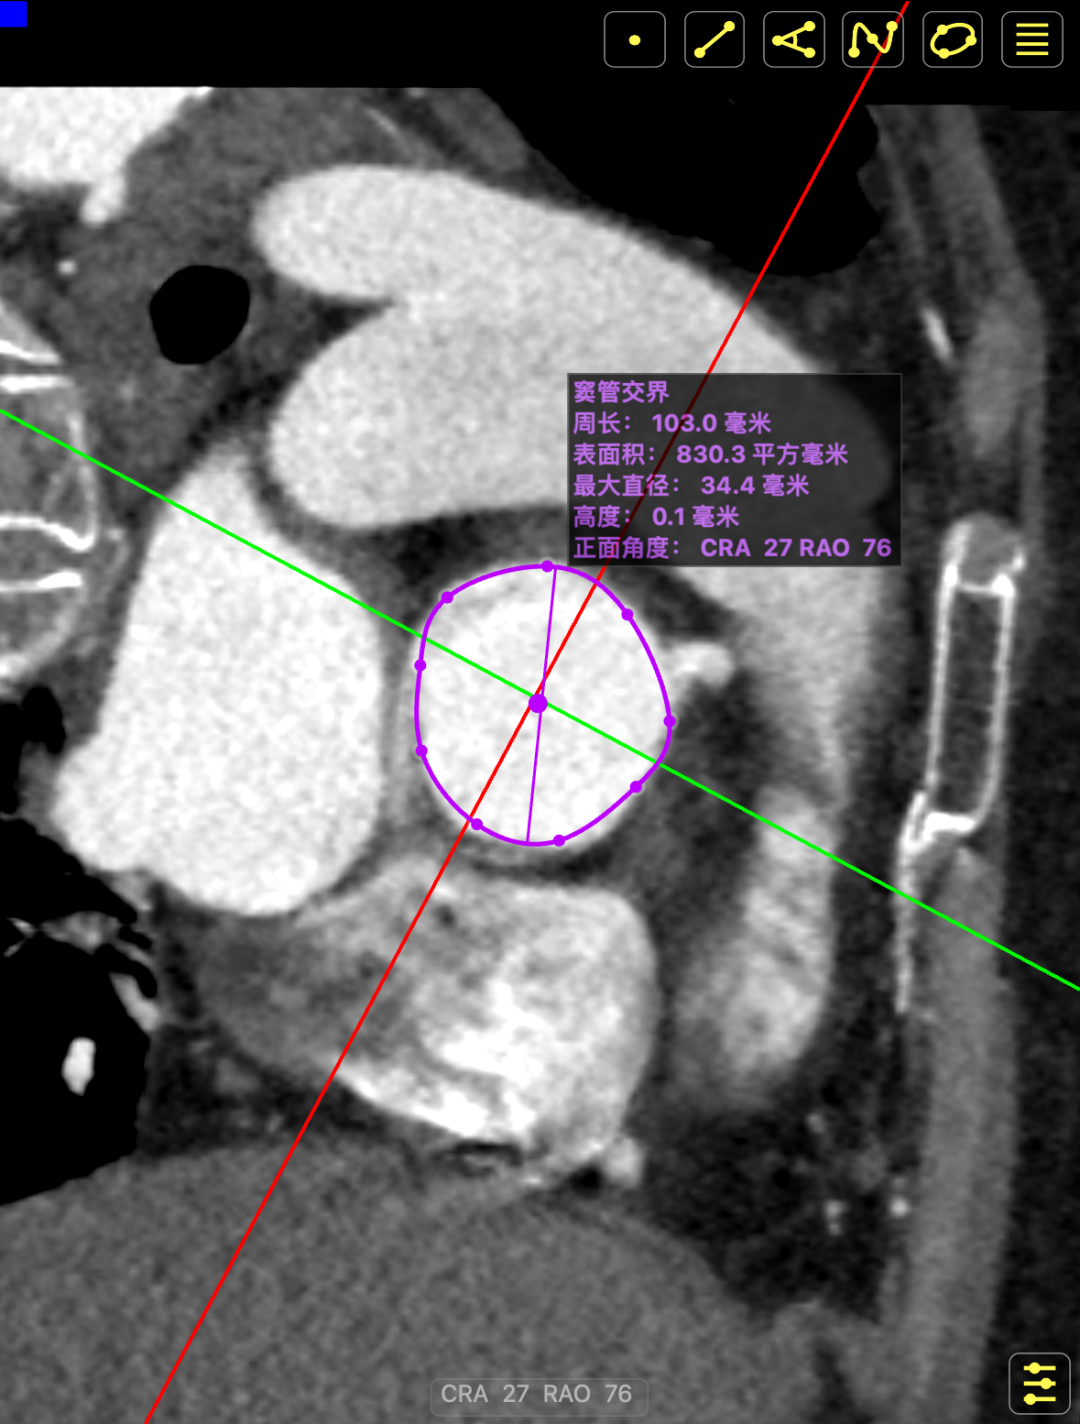

术前CT提示

主动脉瓣多发钙化,主动脉瓣为type0型二叶瓣中重度钙化。主动脉瓣环面积折算直径约24mm。患者双侧冠脉开口高度可(左冠14.46mm,右冠18.29mm),主动脉升弓降部管壁不规则并钙化斑块影,主动脉弓并龛影。升主动脉管径36mm,降主动脉管径22mm。腹主动脉、双侧髂动脉管壁不规则并可见钙化斑块影,双侧髂总动脉及其分支髂内动脉管腔轻度狭窄。

CT影像